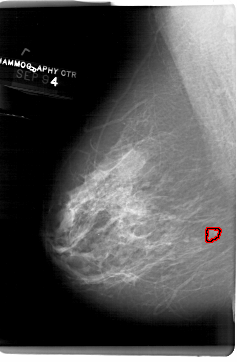

FILE: A_1514_1.LEFT_MLO.OVERLAY

TOTAL_ABNORMALITIES 1

ABNORMALITY 1

LESION_TYPE MASS SHAPE IRREGULAR MARGINS ILL_DEFINED

ASSESSMENT 4

SUBTLETY 2

PATHOLOGY BENIGN

TOTAL_OUTLINES 1

BOUNDARY